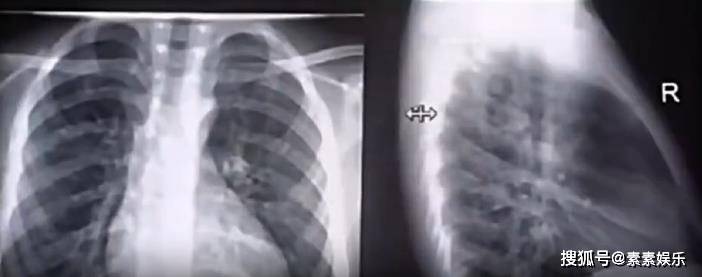

韩国媒体称,泡温泉这个行为,使原本就有心脏疾病的她血管压力上升。当时她的肺部感染也已经开始扩散,两个重要器官的双重伤害之下,这就是她在短时间内心脏发生骤停的原因。

救护车又接到她,将她再次运往附近的医院,但很可惜,在经历了长达14小时的心肺复苏,再加上其他的抢救治疗,大S最终仍旧没有恢复意识,因重度肺部感染和心脏器官衰竭离世。